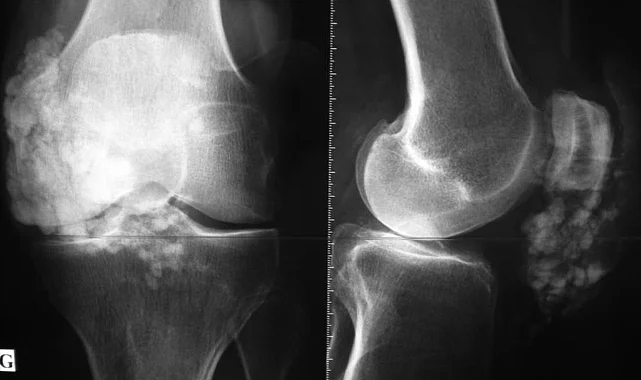

Özellikle orta yaş grubu hastalar için önemli bir tedavi seçeneği olan yüksel tibial osteotomi ameliyatları, diz kireçlenmesinin yol açtığı ağrı ve hareket kısıtlılıklarını büyük ölçüde azaltıyor. Bu ameliyat, diz ekleminde oluşan açısal deformiteleri düzelterek, diz eklemine binen yükü dengeliyor. Böylece hastalar, ameliyat sonrası rahat bir şekilde hareket edebiliyor ve günlük aktivitelerine geri dönebiliyor.

Uzmanlar, osteotomi ameliyatlarının diz protezi ameliyatına giden süreci de geciktirdiğini ifade ediyor. Diz protezi ameliyatları, genellikle ileri yaşlarda ve ileri düzeyde kireçlenme vakalarında başvurulan bir yöntem. Ancak, yüksel tibial osteotomi gibi kemik düzeltici ameliyatlar sayesinde, hastaların diz protezi ameliyatına ihtiyaç duymadan yıllarca sağlıklı bir şekilde yaşamalarını sağlamak mümkün oluyor.